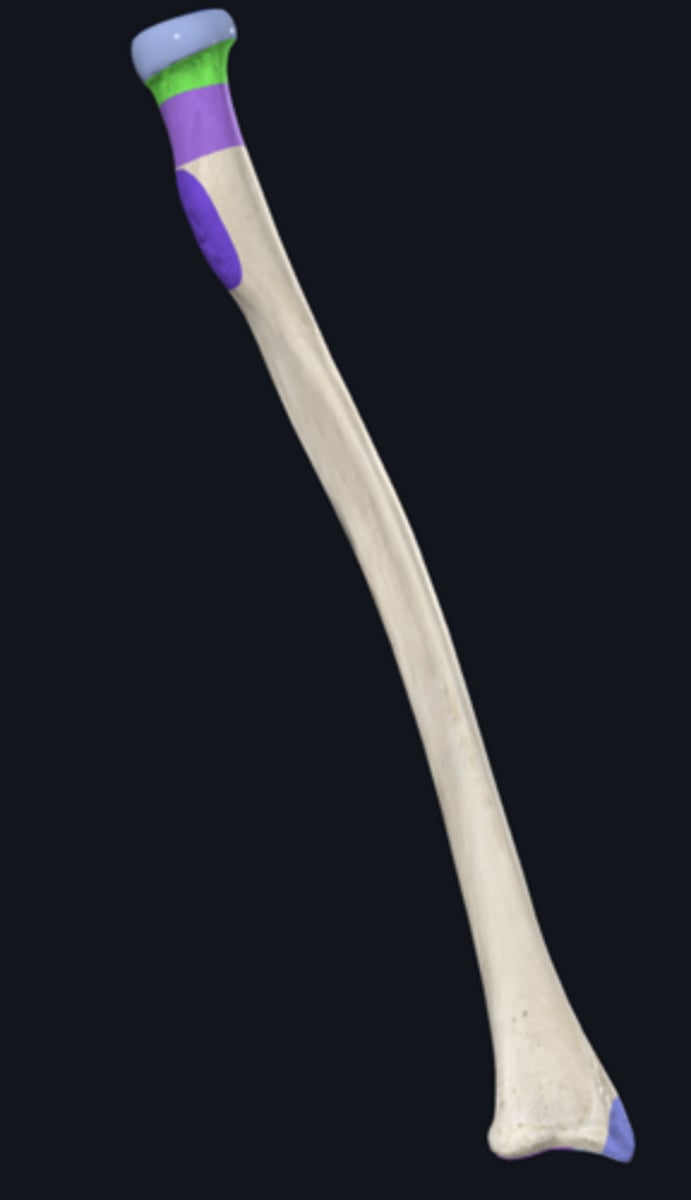

anterior border of radius

anterior surface of radius

carpal articular surface

interosseous border of radius

lateral surface of radius

posterior border of radius

posterior surface of radius

articular circumference of head of radius

articular facet of head of radius

dorsal radial tubercle

grooves for extensor tendons

head of radius

lunate articular facet of radius

neck of radius